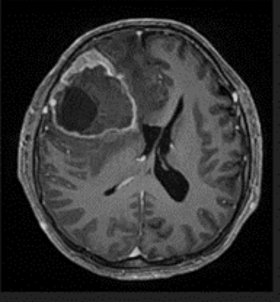

A 51-year-old male with a medical history of Neurofibromatosis type 2 presented with a clinical progression spanning 3 months, characterized by difficulties in concentration, short- term memory loss, and a frontal oppressive-type headache rated 5/10 on the analog pain scale, exacerbated by the Valsalva maneuver. Imaging studies revealed a hypodense lesion with central necrosis in the right frontal lobe accompanied by perilesional edema, resulting in interhemispheric line displacement. Additionally, there was partial collapse of the ipsilateral lateral ventricle and subfacial herniation.

Gimson and Smith's study documented epileptic seizures detected on anesthetic depth monitors with EEGp, predominantly utilizing BIS in the literature.16 You et al. demonstrated SedLine's effectiveness in detecting epileptiform discharges with 100% sensitivity and specificity, emphasizing its utility in identifying abnormal brain activity.17 Regarding anesthetic drugs, no clear dose-response relationship exists for seizures, and some drugs may have pro-epileptic effects, emphasizing careful consideration in patients with seizure history or predisposition.18 Early seizures post-craniotomy for brain tumor resection are common, warranting vigilance and appropriate management to prevent and address potential complications (Figure 1-4).19-21

Figure 1 Preoperative tomography, coronal view.

Figure 2 Preoperative tomography, axial view.